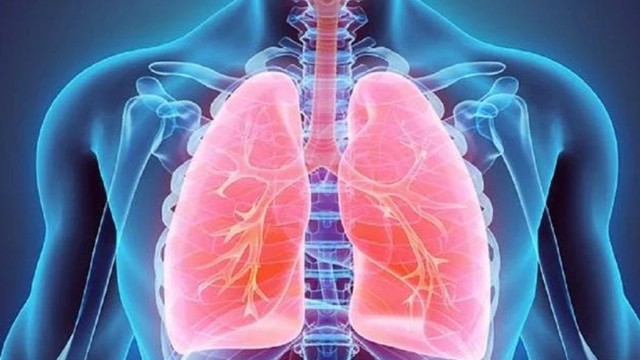

Tràn dịch màng phổi là một bệnh lý khá phức tạp và đang có xu hướng gia tăng trong công đồng. Bệnh lý này thường diễn tiến nhanh chóng và tác động trực tiếp đến sức khoẻ của người bệnh, thậm chí là dẫn đến tử vong nếu không được điều trị kịp thời. Vậy dấu hiệu tràn dịch màng phổi là gì?